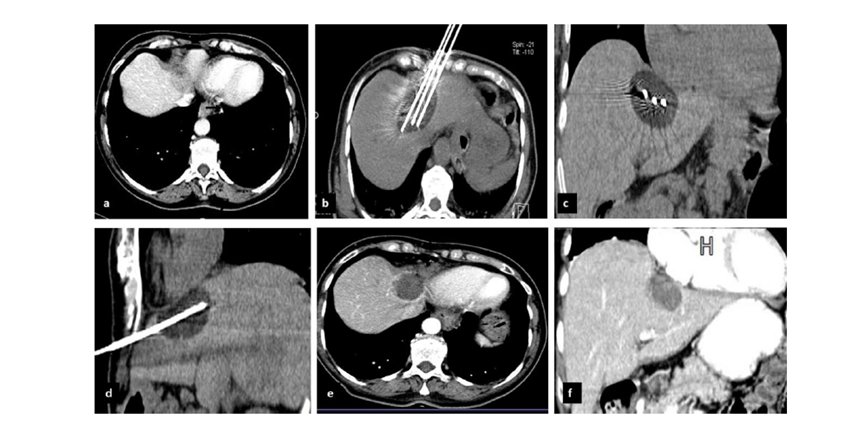

undefined

62歲女性,肝轉(zhuǎn)移(卵巢癌)腫瘤的完全消融病例

(a)軸向CT顯示病變位置毗鄰心臟和上腔靜脈(黑色箭頭)。

(b)術(shù)中軸向CT掃描:使用三個(gè)冷凍探針。

(c)冠狀面和(d)矢狀面顯示冰球毗鄰心包。

1個(gè)月后的軸向(e)和冠狀位(f)增強(qiáng)CT掃描顯示低密度區(qū)域,由于肉芽組織反應(yīng)引起的邊緣增強(qiáng)。